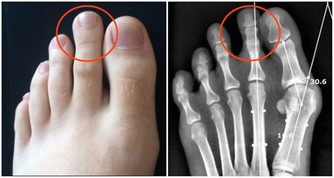

3.血栓45-55歲很容易出現血栓、腦血栓、肺栓塞、心梗等,

抽煙、高血壓、糖尿病、高血脂、久坐不動等都是患血栓的高危因素。

就像水管的水流速度慢,雜質容易沉積一樣。

輕者出現肢體偏癱拄拐等,重者直接威脅生命。